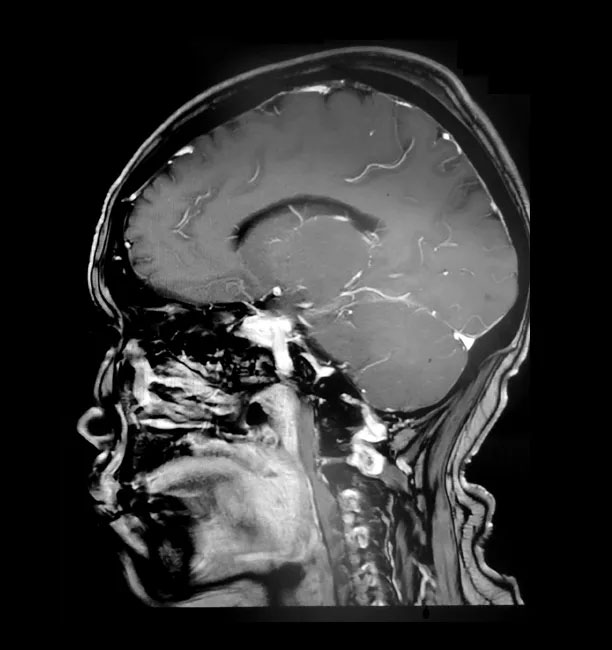

為尋求進一步治療,經(jīng)親友推薦,胡女士慕名前來上海藍十字腦科醫(yī)院。入院后,行頭顱磁共振增強掃描后確認,患者右側(cè)顱底蝶骨嵴-鞍結節(jié)區(qū)實性占位,考慮為腦膜瘤且血供豐富;右側(cè)大腦前動脈A1段與瘤灶貼近。

▲ 蝶骨嵴腦膜瘤周圍多重要神經(jīng)血管

上海藍十字腦科醫(yī)院神經(jīng)外科主任沈建康教授指出,患者的腦腫瘤直徑約3厘米,只有“鴿子蛋”大小,體積并不大。但蝶骨嵴腦膜瘤由于位置比較特殊,腫瘤有可能和血管神經(jīng)粘連緊密,手術難度和風險都很大。如果沒有做到全切除,腫瘤易復發(fā),可能需要再次手術;術中若損傷瘤體周圍神經(jīng)血管,則可能導致患者殘疾,甚至危及生命。

▲ 術后影像顯示,腫瘤已被切除